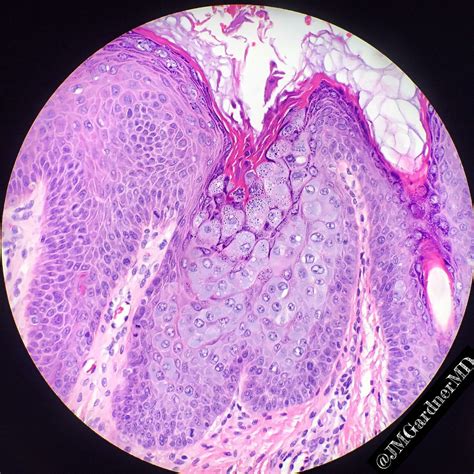

Verruca

Verruca Formation Stock Image | CartoonDealer.com #25182745